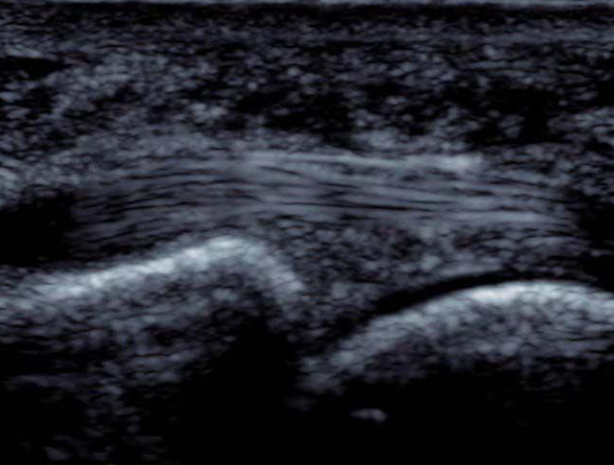

Foot Doesn’t Work Right

A 35-year-old male felt a painful “pop” in his posterior left lower leg while playing football. Afterwards his “foot didn’t work right anymore.” X-ray of the left ankle and tib/fib are normal but he is unable to ambulate. You place an ultrasound over the area of maximal tenderness and discover the following:

Read More...